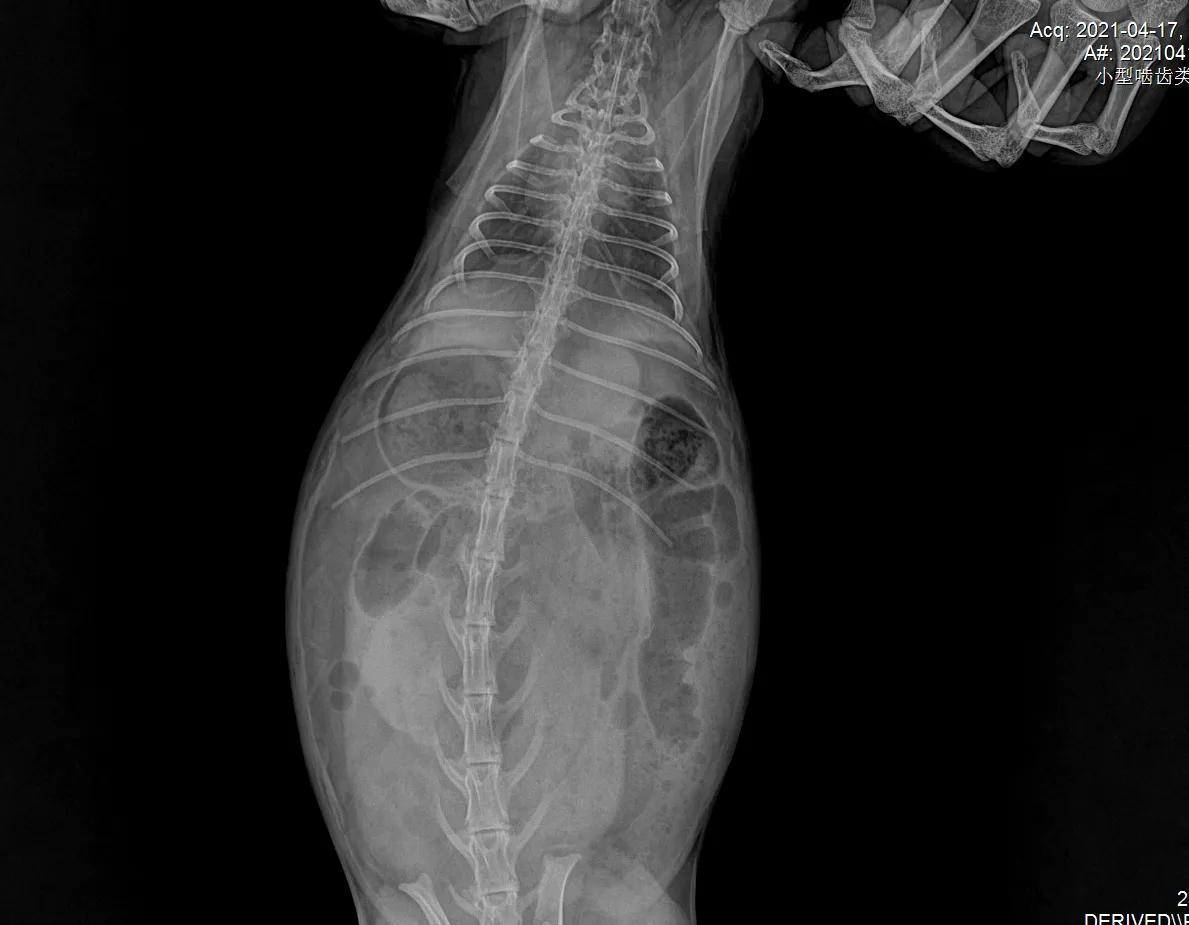

没有犹豫,立刻带它到当地动物诊所拍片,

医生看出来是胀气

表示对治疗兔子并不在行,教我怎么按摩它的肚子。我就坐在诊所帮“汤圆”按摩腹部,那是第一次“汤圆”在我身上趴那么久,它平时太凶悍了,连抓都很难抓到,从来没有一次在我怀里安稳呆过5秒钟。半小时后我要求再次拍片,显示气体有所移动。